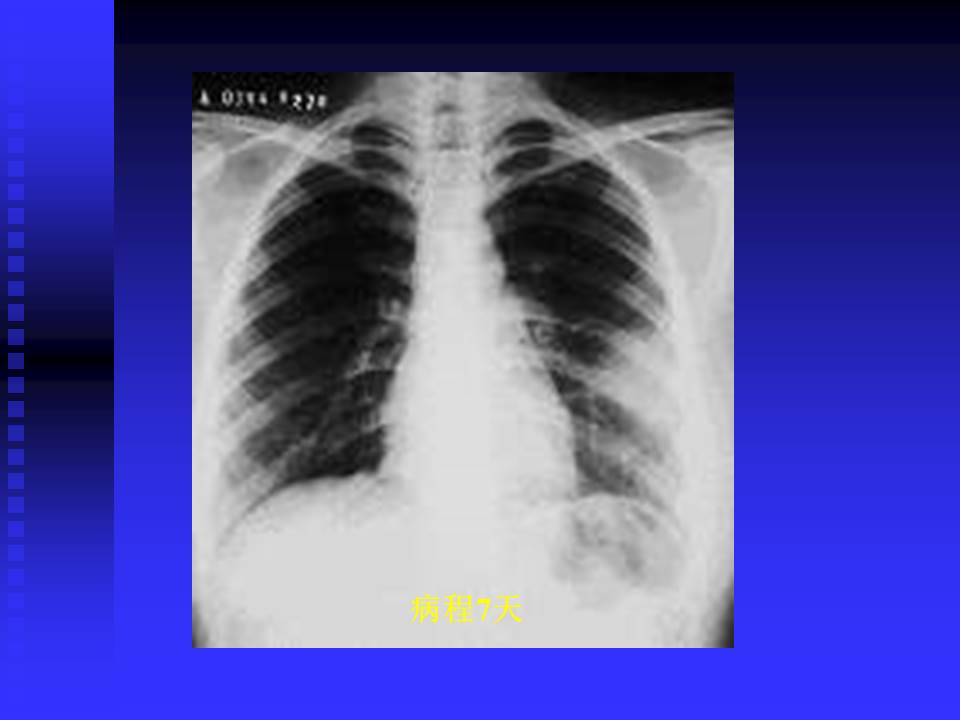

【PPT】严重急性呼吸综合征的影像鉴别诊断